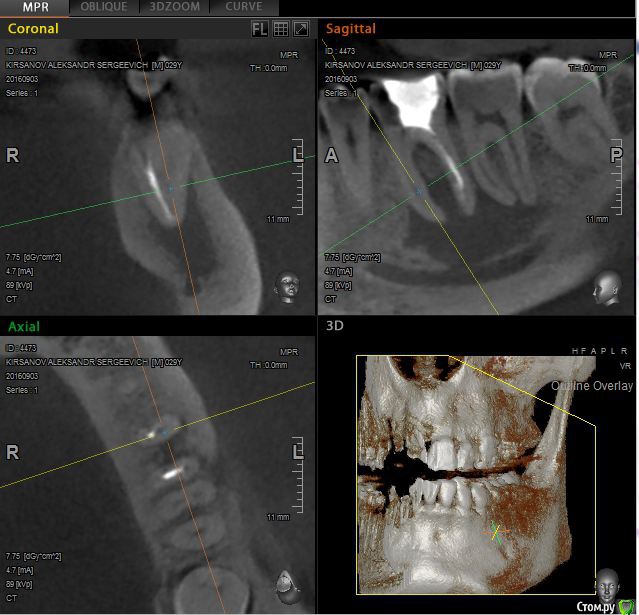

St. Опубликовано 12 ноября, 2016 Поделиться Опубликовано 12 ноября, 2016 Выложу скрины приложенного КТ. Так ответов будет больше. Есть пропущенный канал в 6 зубе. И нужно проверить на жизнеспособность соседний 7. Я бы рекомендовала попробвать перелечить и понаблюдать. Но Вы должны для себя понимать что перелечивание каналов очень сложная, дорогая и непрогнозируемая процедура. Хотя вероятность успеха достаточно высока. Если хотите гарантий - тогда удаление и имплант как восстановится кость. Еще хорошо бы знать как давно лечили каналы в этом зубе, как он вел себя после лечения, беспокоит ли сейчас? 2 Ссылка на комментарий

alexkirs Опубликовано 13 ноября, 2016 Автор Поделиться Опубликовано 13 ноября, 2016 Выложу скрины приложенного КТ. Так ответов будет больше. Есть пропущенный канал в 6 зубе. И нужно проверить на жизнеспособность соседний 7. Я бы рекомендовала попробвать перелечить и понаблюдать. Но Вы должны для себя понимать что перелечивание каналов очень сложная, дорогая и непрогнозируемая процедура. Хотя вероятность успеха достаточно высока. Если хотите гарантий - тогда удаление и имплант как восстановится кость. Еще хорошо бы знать как давно лечили каналы в этом зубе, как он вел себя после лечения, беспокоит ли сейчас? Большое спасибо за ответы.Каналы лечил где-то 2 года назад, после лечения, где-то через полгода надулась десна и гной выходит периодически через свищ. Боли нет. На счет 22 и 23 там все понятно, их лечу сейчас. А вот что делать с 6? Вы считаете, что стоит попробовать лечить? Ссылка на комментарий

Гарриевич Опубликовано 13 ноября, 2016 Поделиться Опубликовано 13 ноября, 2016 Шансы на успех лечения "кисты" в Вашем случае процентов 90. То, что вы описали характеризует лечение как неадекватное. Имплантация в данном случае будет отсроченная и потеря костной ткани будет приличная Ссылка на комментарий